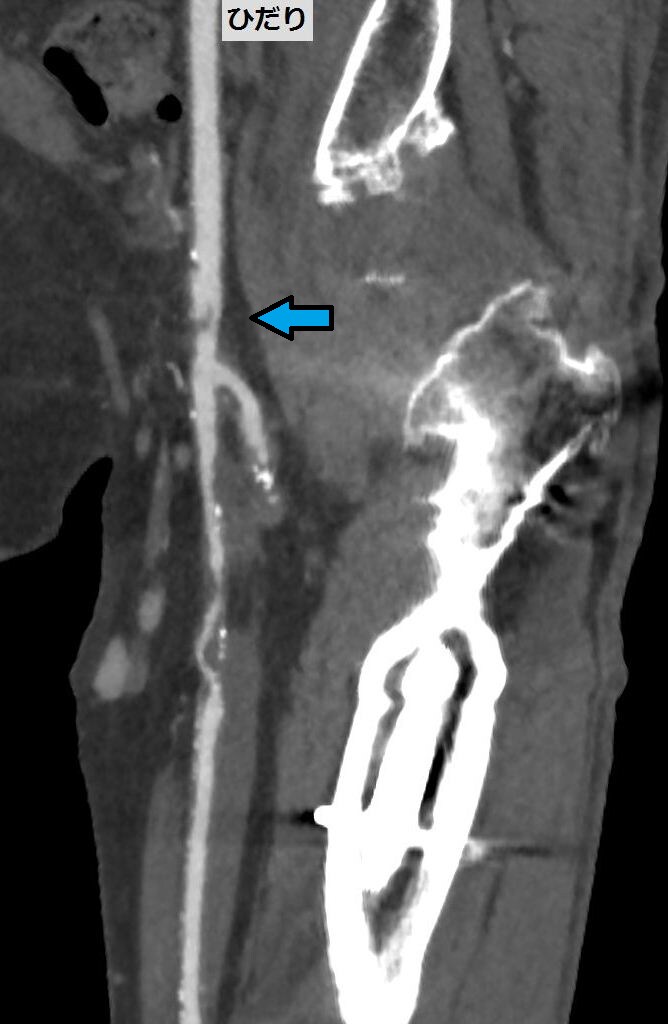

図2.下肢CTA CFA

CFAのCPR画像。矢印部に解離と狭窄が見られる。